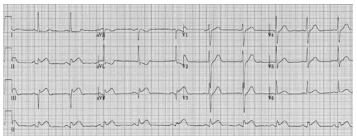

Com base no quadro clínico e eletrocardiograma da questão

anterior, assinale a parede cardíaca acometida.

Considere-se a imagem a seguir.

Foi realizado eletrocardiograma do paciente e solicitada troponina. Com base no quadro clínico e na imagem apresentada, assinale a opção que apresenta a conduta adequada.